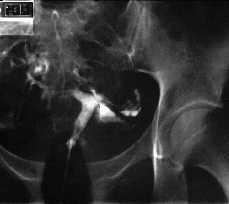

En histerosalpingografía practicada con posterioridad se objetiva un útero de morfología normal, así como ambas trompas permeables, compatible con la normalidad. No se dibujan trayectos fistulosos.

-- Descartamos la existencia de fístula uteroperitoneal mediante la práctica de una HSG.

Figura 5. Imágenes de la histerosalpingografía de control practicada 4 meses más tarde.